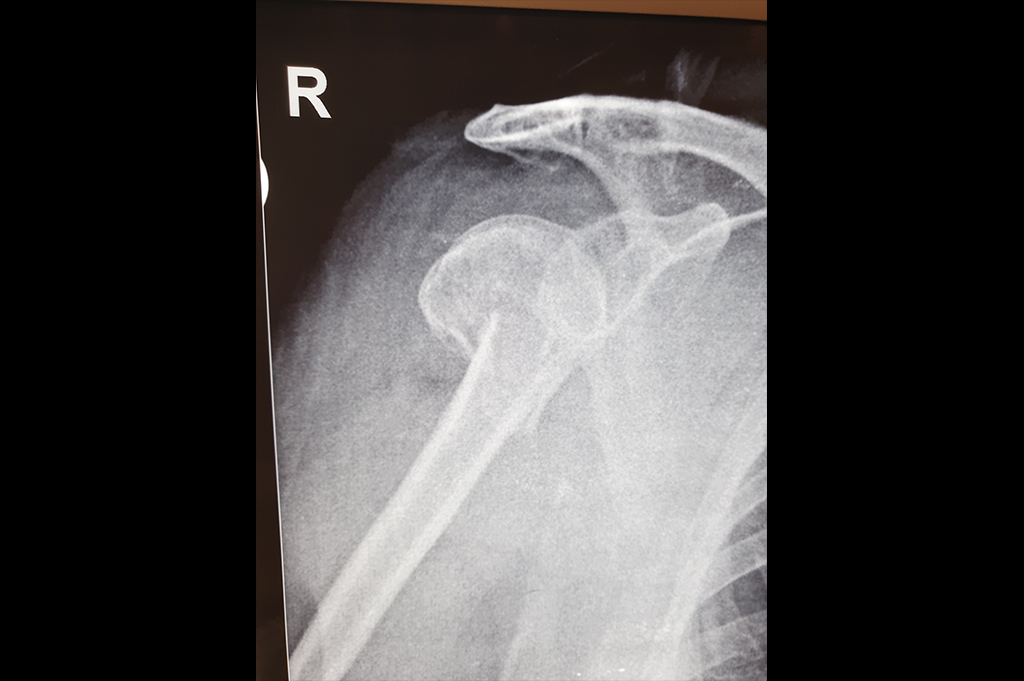

Proximal Humerus